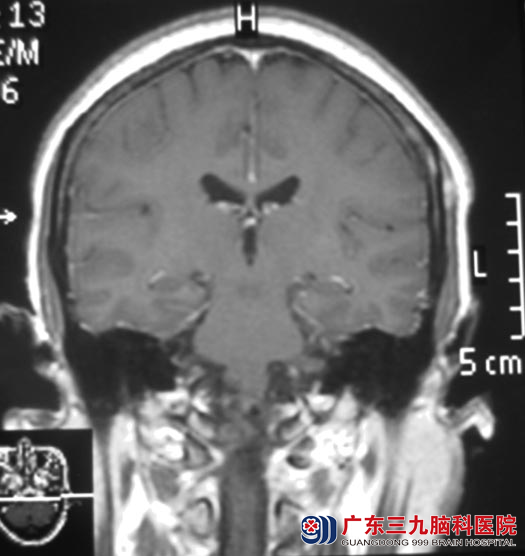

入住广东三九脑科医院综合神经外科时查体:右侧浅感觉较左侧差,悬雍垂向右侧,左侧咽反射减弱,左侧耸肩转头运动减弱,舌左偏;复查脑部MR见:枕骨大孔区级上颈段椎管内示一不规则形占位性病变,病变以宽基底与斜坡后方硬脑膜及颈1-2椎体后方硬脊膜相连,大小约20.5mm×12.0mm×32.5mm,延髓及上颈段脊髓受压、变形,并向右偏移;头颈CTA检查提示:枕大孔区占位性病变,血供较丰富,左侧椎动脉被包绕可疑。